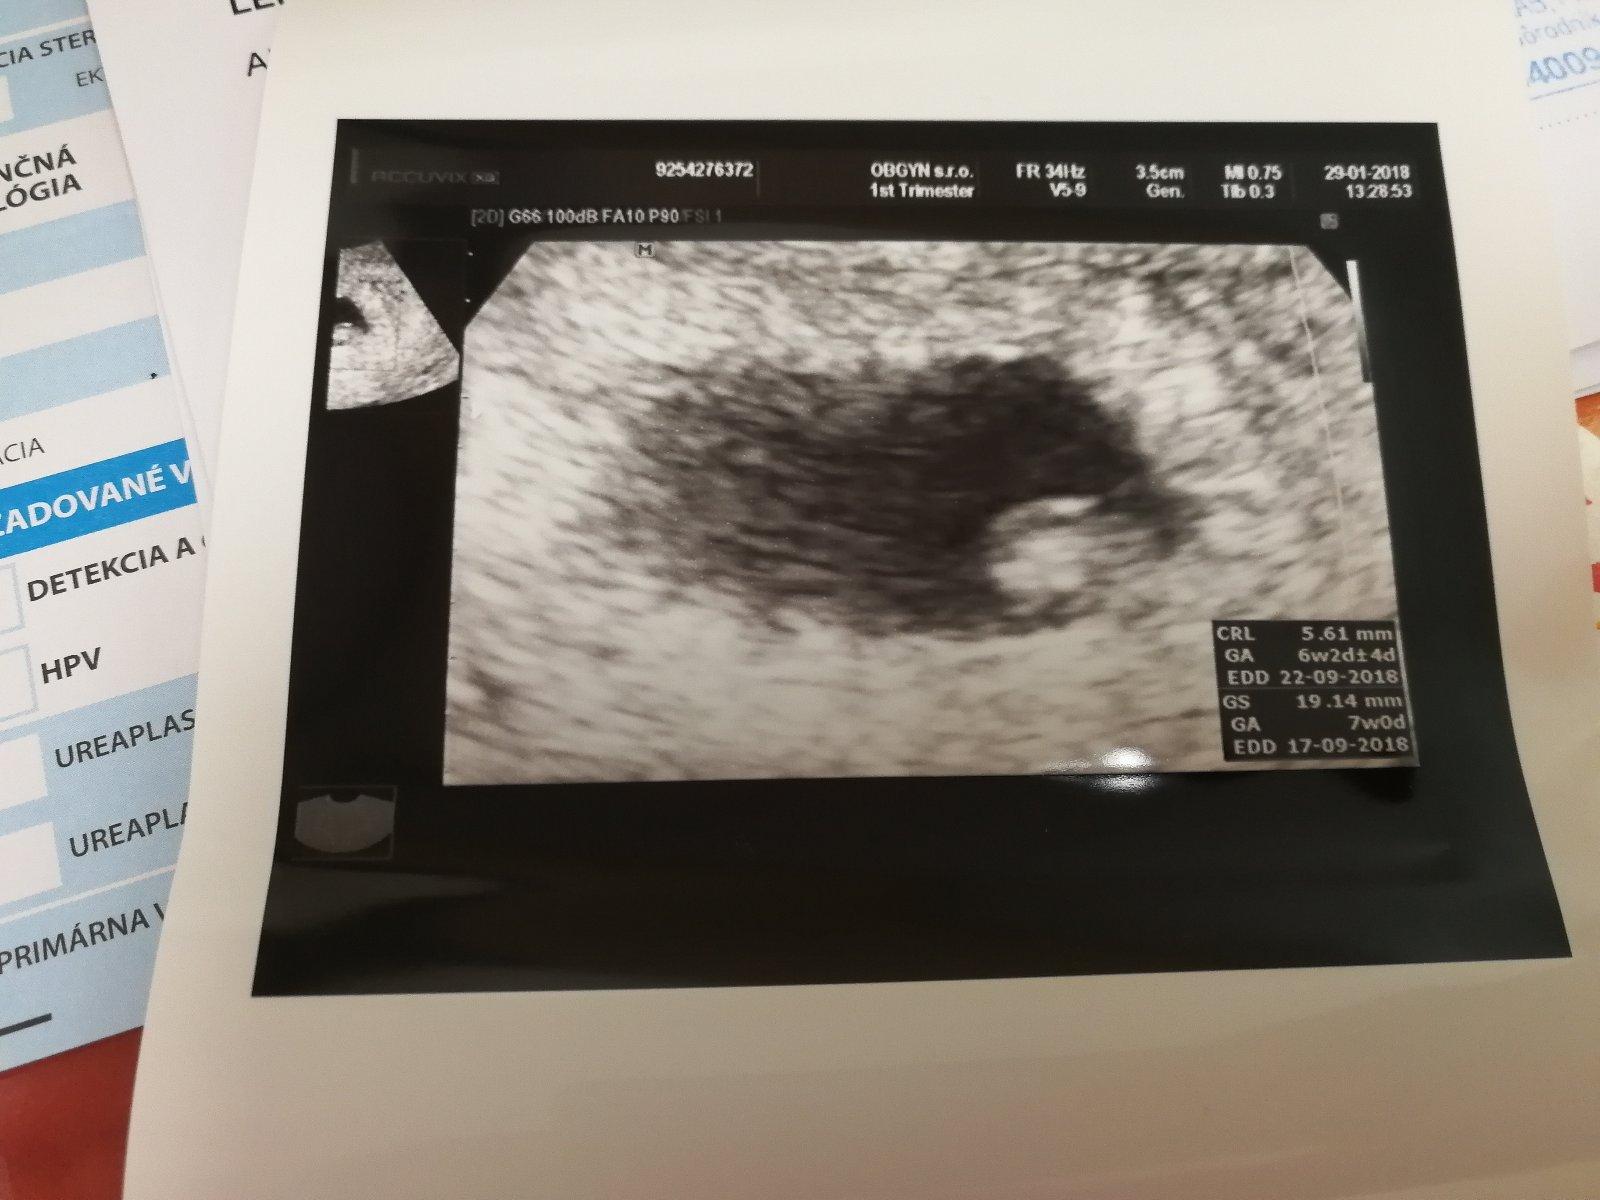

Cely januar som nedostala menstruaciu robila som si pred 5 dnami aj 2 testy oba vysli negativne bola som u gyn. ta mi robila vaginalny ultrazvuk ale hovorila ze tehotenstvo zatial nevidi ze mozno ze som otehotnela neskor ale ze tam nieje nic vidiet este tak som dostala vyvolavacku ale uz par dni mam tlaky pod bruchom a prsia ma bolia uplne inac .